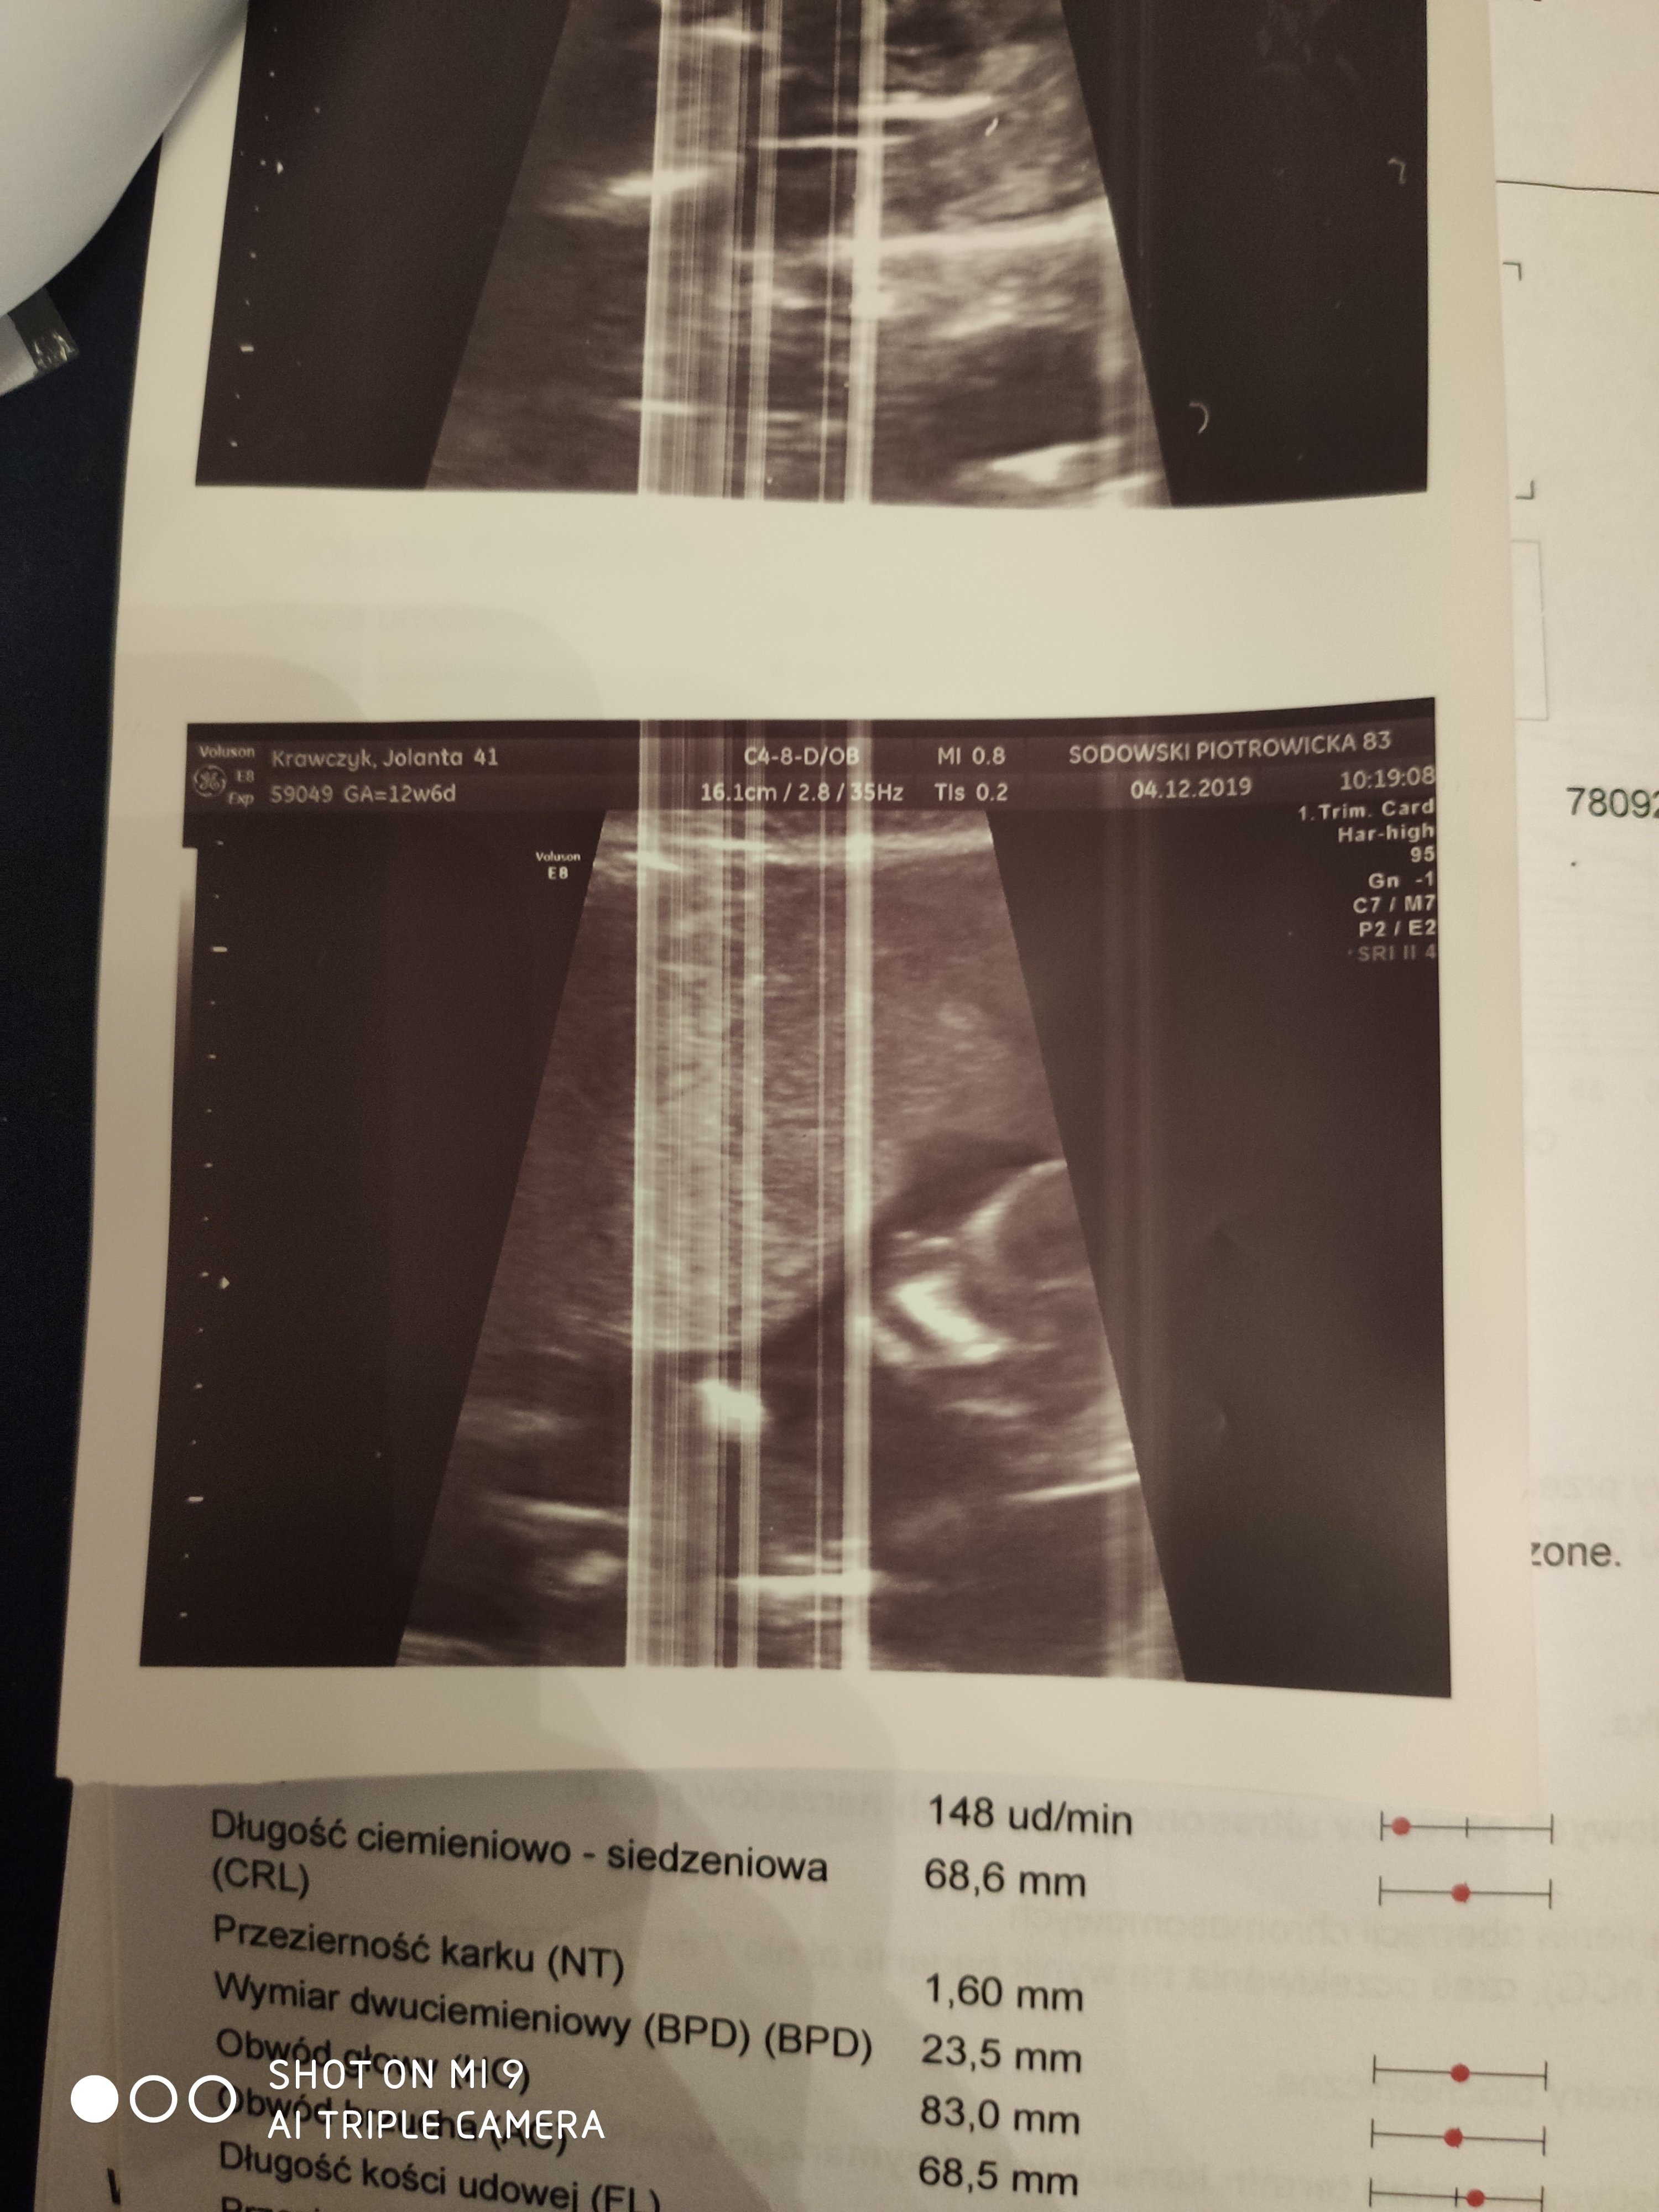

Masz zdjęcie noska z pierwszych badań prenatalnych? Powinno być robione z profilu pod odpowiednim kątem. Kość powinna być mierzona właśnie przy takim ułożeniu. Raz się spotkałam, że lekarz nie mierzył tej kostki z profilu tylko z przodu (widocznie nie mógł uchwycić widoku z profilu) i wyszedł mu długi pomiar a w rzeczywistości kostka była bardzo krótka. Może to podobny przypadek. W 21 tygodniu lekarz dobrze widział profil dziecka? Możesz to skonsultować jeszcze z innym lekarzem tak jak radzi Angelina, najlepiej takim który jest również genetykiem. Pamiętaj, że około 1-3% zupełnie zdrowych dzieci nie ma tej kostki a spośród wszystkich dzieci nieposiadających kości lub mających hypoplastyczne około 80% to zdrowe dzieci.

Jedno z pierwszych badań a drugie te z rączką to drugie gdzie niby nie widac